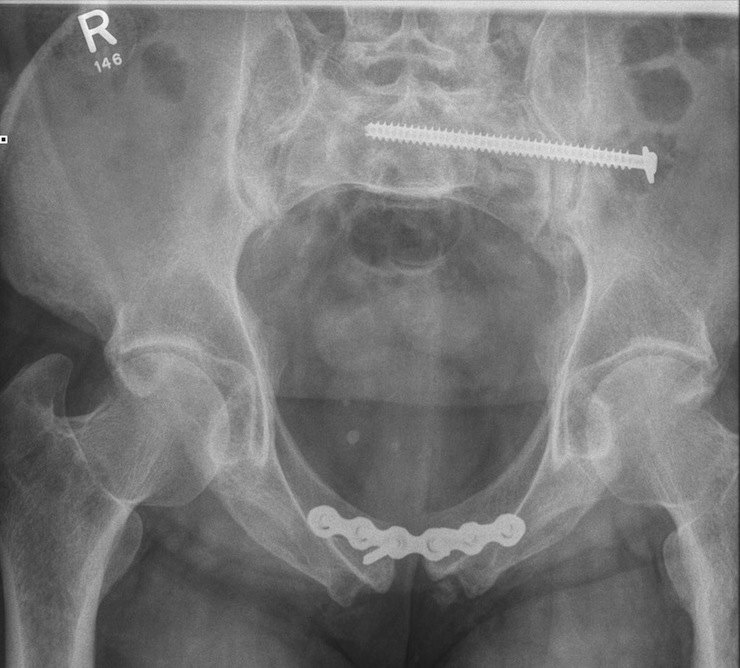

Superiorly applied plate

- pelvic reconstruction plate

Post-operative XRs: AP, outlet and inlet views